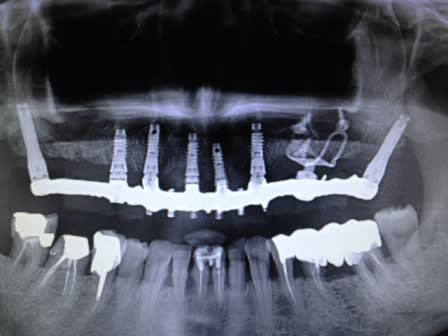

un autre cas max sup :

4 axiaux ant. un latéral avec légère effraction sinusienne (fractal lift ) 2 ptérygoidiens